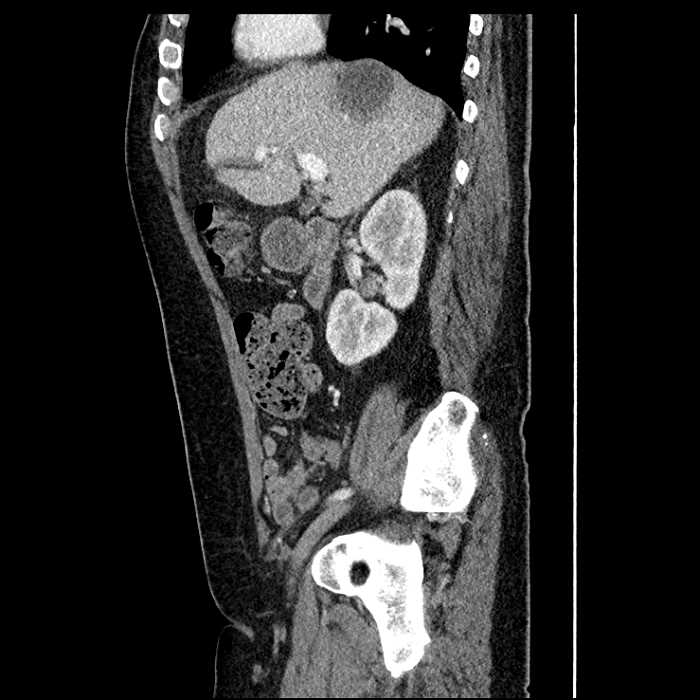

• Large fluid density structure in hepatic segments 7 and 8 measuring 10 x 7 x 7 cm with internal septation and circumferential ill-defined low density compatible with edema

• Peripherally enhancing subcapsular collections along the anterior margin of the left hepatic lobe measuring 3 x 1 cm and 2 x 1 cm

• Clearly marginated fluid density structure in segment 7 and several other scattered tiny hypodensities, which likely represent cysts

• Mild mural thickening of a segment of the sigmoid colon with adjacent fat stranding and a 1.5 cm fluid and gas collection along the tip of an inflamed diverticulum

• Loss of the normal fat plane between this collection and adjacent loops of small bowel, which demonstrate mural thickening

Acute sigmoid diverticulitis complicated by a small contained perforation and a large abscess in the right hepatic lobe. Additional small subcapsular abscesses along the anterior margin of the left hepatic lobe.

Additionally, loss of the normal fat plane between the peridiverticular collection and adjacent thickened loops of small bowel raises the potential for an enterocolonic fistula.

Hepatic abscess showing the double target sign with low density internally surrounded by a thin inner enhancing rim (red arrow) and ill-defined outer low density rim (yellow arrow). Blue arrow indicates an internal septation. Red arrows: additional smaller subcapsular abscesses. Red arrow: focal contained perforation associated with diverticulitis.